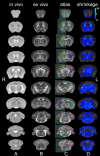

We do not have a full understanding of the mechanisms underlying plasticity in the human brain. Mouse models have well controlled environments and genetics, and provide tools to help dissect the mechanisms underlying the observed responses to therapies devised for humans recovering from injury of ischemic nature or trauma. We aimed to detect plasticity following learning of a unilateral reaching movement, and relied on MRI performed with a rapid structural protocol suitable for in vivo brain imaging, and a longer diffusion tensor imaging (DTI) protocol executed ex vivo. In vivo MRI detected contralateral volume increases in trained animals (reachers), in circuits involved in motor control, sensory processing, and importantly, learning and memory. The temporal association area, parafascicular and mediodorsal thalamic nuclei were also enlarged. In vivo MRI allowed us to detect longitudinal effects over the ~25 days training period. The interaction between time and group (trained versus not trained) supported a role for the contralateral, but also the ipsilateral hemisphere. While ex vivo imaging was affected by shrinkage due to the fixation, it allowed for superior resolution and improved contrast to noise ratios, especially for subcortical structures. We examined microstructural changes based on DTI, and identified increased fractional anisotropy and decreased apparent diffusion coefficient, predominantly in the cerebellum and its connections. Cortical thickness differences did not survive multiple corrections, but uncorrected statistics supported the contralateral effects seen with voxel based volumetric analysis, showing thickening in the somatosensory, motor and visual cortices. In vivo and ex vivo analyses identified plasticity in circuits relevant to selecting actions in a sensory-motor context, through exploitation of learned association and decision making. By mapping a connectivity atlas into our ex vivo template we revealed that changes due to skilled motor learning occurred in a network of 35 regions, including the primary and secondary motor (M1, M2) and sensory cortices (S1, S2), the caudate putamen (CPu), visual (V1) and temporal association cortex. The significant clusters intersected tractography based networks seeded in M1, M2, S1, V1 and CPu at levels > 80%. We found that 89% of the significant cluster belonged to a network seeded in the contralateral M1, and 85% to one seeded in the contralateral M2. Moreover, 40% of the M1 and S1 cluster by network intersections were in the top 80th percentile of the tract densities for their respective networks. Our investigation may be relevant to studies of rehabilitation and recovery, and points to widespread network changes that accompany motor learning that may have potential applications to designing recovery strategies following brain injury.